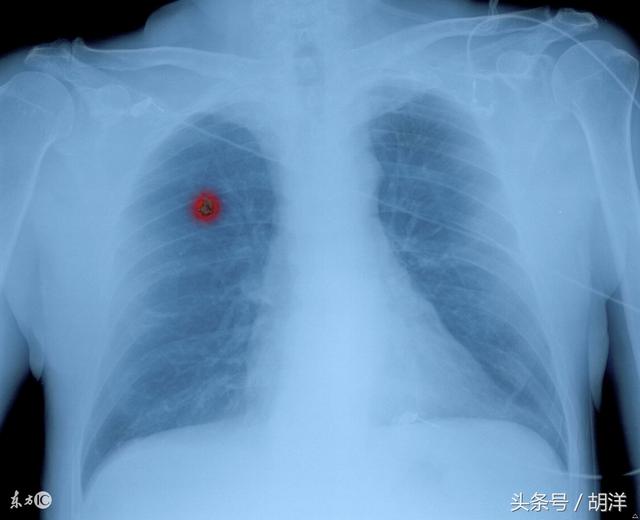

这些小结节可以通过手术根治,再长大一些就是不能根治的肺癌

原创 胡洋·上海市肺科医院早期肺癌现在还没有一个明确的定义,一般来说只要能够通过手术根治的肺癌都是早期的,通常早期肺癌特别是其直径小于1cm的时候很少有特异性的表现,但如果有以下表现最好手术治疗。